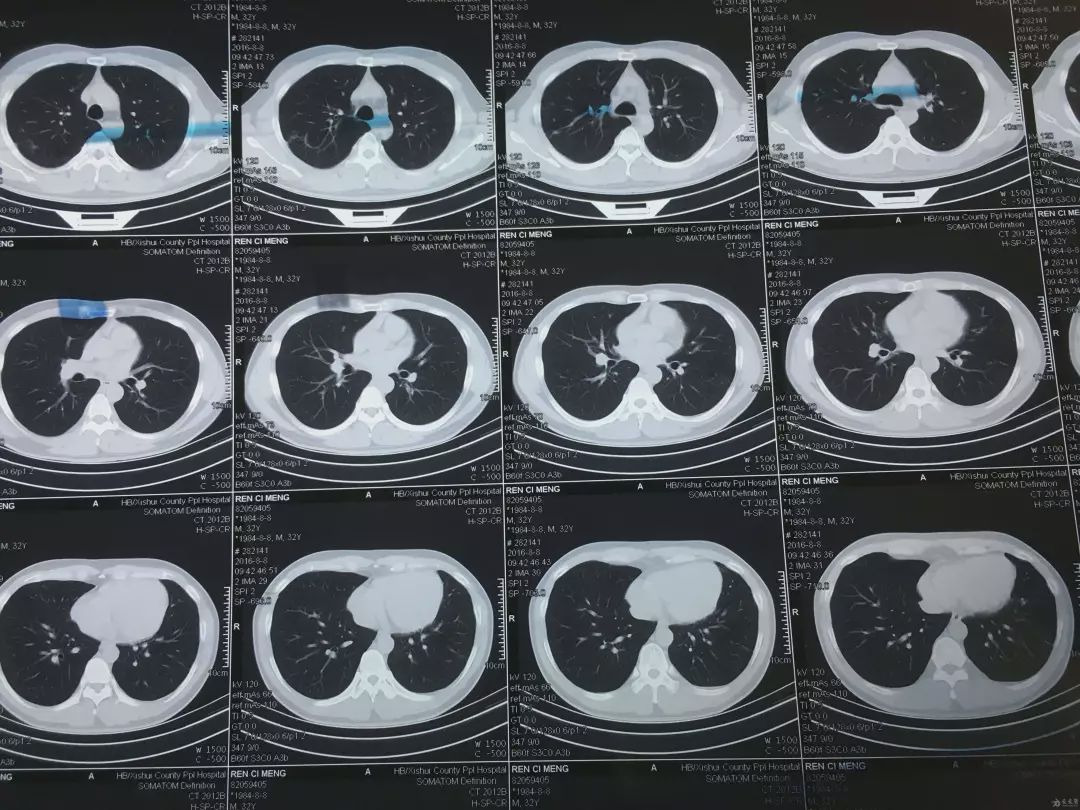

这次,他们整出了个名叫PANDA ( pancreatic cancer detection , with artificial intelligence )的 AI 大模型,根据简单的平扫 CT 图像,它就能做出胰腺癌相关的诊断。

PANDA 帮忙筛查胰腺癌的过程说起来也很简单,和医生看片子也没啥两样。

不过它凭借强大的算法,注意到的细节比医生肉眼看到的多得多,自然也能顺利找到疑似病变的地方。

PANDA 在拿到平扫 CT 图之后,先会用分割功能在整张图像中找到胰腺的位置。

找到胰腺后,再启动检测功能,去看胰腺里有没有啥不对劲的地方。

要是找到有异常的地方,就用第三步的分类功能,去识别这情况属于哪种胰腺病变。

其中有一个人,每年都会去医院的体检中心定期体检,当时他在体检时并没发现什么异常。

结果七个月后,在 PANDA 进行临床试验的时候,他的 CT 图被检测出了有 95% 的概率是胰腺神经内分泌肿瘤。

后来,医院直接找来他,用增强磁共振检查了一通,发现 PANDA 还真没判断失误。

幸好肿瘤还在早期,早早手术割掉了,后续检查时也没再复发。